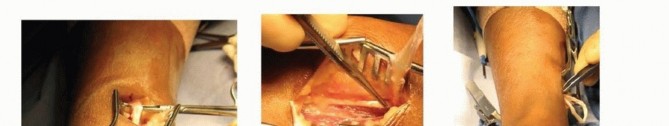

1. ## Split Tibialis Tendon Transfer to Peroneus Brevis (after Kaufer)A longitudinal incision is made over the insertion of the tibialis posterior on the navicular, and the sheath is opened ( TECH FIG 1A).The plantar half of the tendon is released and the tendon is split longitudinally ( TECH FIG 1B,C).A second incision is made just posterior to the medial malleolus, extending proximally for 4 cm ( TECH FIG 1D,E).The sheath of the tibialis posterior is split longitudinally, and the free end of the tendon is delivered into this wound.The longitudinal split in the tendon is extended proximally to the musculotendinous junction.The third longitudinal incision is made about 2 cm proximal to the tip of the lateral malleolus and extends proximally ( TECH FIG 1F,G).The peroneal tendon sheath is incised longitudinally.The split tendon is then passed posterior to the tibia and fibula, and anterior to the neurovascular bundle, into the third incision. The split tibialis posterior tendon can be sutured into the peroneus brevis tendon at this level (see FIG 1C) or can be transferred distally, which requires a fourth incision.

TECH FIG 1 • A. A longitudinal incision is made over the insertion of the tibialis posterior. B. The tibialis posterior tendon is then dissected free at its insertion, and half of the tendon is released, most often from the plantar surface. C. The distal end of the tendon is tagged with a running locked suture, and the division in the tendon is developed proximally as far as possible.

### TECH FIG 1 •

D. A second incision is made just posterior to the medial border of the tibia, proximal to the medial malleolus. The fascia is divided longitudinally, and the tibialis posterior muscle is identified. E. The suture ends are delivered from distal to proximal through the tendon sheath, and the split tendon is brought out from the second incision. F. A short longitudinal incision is then made over the lateral side of the leg, posterior to the fibula, across from the medial incision. G. The split tendon is then passed from medial to lateral along the posterior border of the tibia and the fibula, anterior to the neurovascular bundle. The tendon is delivered through the lateral wound. H. The fourth incision is distal and just behind the fibular malleolus. The peroneal sheath is incised longitudinally. I. The split tendon is brought through the sheath from the more proximal incision through this distal incision. J,K. The tibialis posterior tendon is then woven through small longitudinal splits in the peroneus brevis and anchored with nonabsorbable suture.The fourth longitudinal incision is made distal to the lateral malleolus, overlying the insertion of the peroneus brevis into the fifth metatarsal base ( TECH FIG 1H).The split tibialis posterior tendon is then passed through the sheath, along the peroneus brevis, into the distal incision ( TECH FIG 1I).The tendon is woven through the peroneus brevis and secured with nonabsorbable sutures ( TECH FIG 1J,K).The foot is held in a neutral position.A weight-bearing, long-leg cast with the knee extended and the foot at neutral is worn for 4 weeks, and then a short-leg, weight-bearing cast is worn for 4 additional weeks.No bracing is required if the patient is able to actively dorsiflex the foot to neutral. If not, an ankle-foot orthosis is recommended.